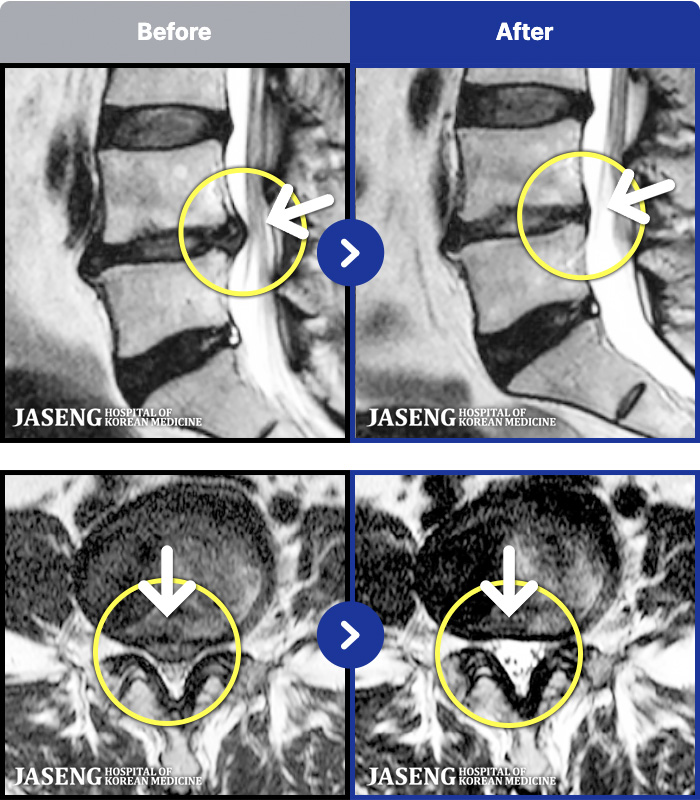

1,296 MRI ũ ʸ Ȯϼ.

ȯںп Ǹ ǿ ԿǾ, ο ġ ۿ Ƿ ġḦ Ͻñ ٶϴ.